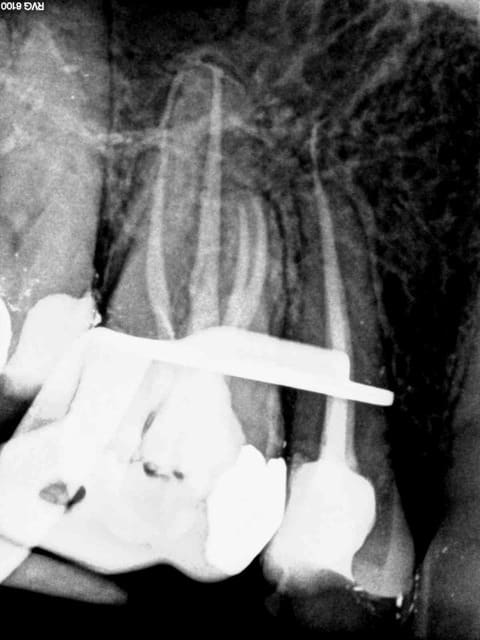

Il y a pire que le tiers payant , une endo faite sans faire la prothèse par dessus. Cette touriste a eu de la chance 1. trouver un dentiste qui accepte de la prendre et 2. tombée juste avant un lapin d'une heure.

Tu as mis la digue "chicot29"?C'est low cost au moins....

Toujours sur les molaires ( par définition au fond et 3 ou 4 canaux) quel confort ca fait gagner du temps. Le tarif est low cost par contre.